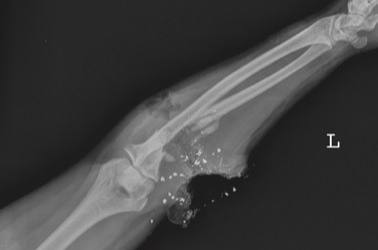

Ранения локтевого сустава, сопряженные с повреждением локтевой артерии, представляют собой тяжелую и неотложную патологию, регулярно встречающуюся в практике тактической медицины в условиях боевых действий. Анализ санитарных потерь свидетельствует, что подобные комбинированные поражения составляют значительную часть ранений верхних конечностей и характеризуются высоким риском неблагоприятного исхода без немедленного и грамотного вмешательства. Ключевая опасность данной травмы заключается в ее двойственной природе. С одной стороны, нарушение целостности крупного магистрального сосуда ведет к быстрому и массивному кровотечению. В замкнутом анатомическом пространстве предплечья излившаяся кровь может привести к развитию синдрома компрессии, или компартмент-синдрома, при котором нарастающий отек сдавливает нервно-сосудистый пучок и мышцы, что грозит необратимой ишемией и некрозом тканей конечности. С другой стороны, проникающее ранение суставной капсулы создает прямую угрозу развития гнойно-септических осложнений. Попадание микрофлоры в стерильную полость сустава на фоне наличия обширной гематомы создает идеальные условия для стремительного развития гнойного артрита, который может разрушить суставные поверхности за короткий срок и привести к стойкой утрате функции руки.